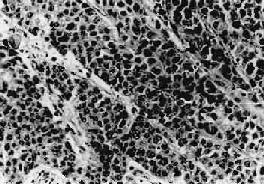

(3)移行细胞Ⅲ级:部分为菜花状,底宽无蒂,或为扁平的斑块,表面常有坏死和溃疡形成。细胞高度未化化;细胞大小、形态不一,排列紊乱(图12-34)。很少或无乳头状结构,有的形成不规则的巢,有的分散。常有多数巨细胞。核形状不规则,染色深,核分裂像很多,并有多数不典型的病理性核分裂像。组织常浸润到膀胱壁肌层深部,并可穿过膀胱壁浸润到邻近器官,如前列腺、精囊、子宫和腹膜后组织等。

膀胱移行细胞<a href=癌 Ⅲ级"/>

图12-34 膀胱移行细胞 Ⅲ级

细胞分化不良,失去移行上皮的特征,细胞大小、形状不规则,排列紊乱,核分裂像多见